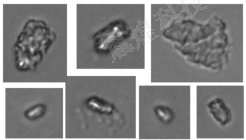

圖2:使用YH-FIPS系列流式動態圖像法粒度儀對某注射劑進行檢測得到的玻璃顆粒的部分圖片,玻璃顆粒的典型圖像特征是具有一定的透明度與光澤。

玻璃碎片是由于機械力而從玻璃容器上脫落的固體玻璃碎片。它們通常在三維上很厚,具有不規則的輪廓,并且在觀察時以稀疏的數量存在(例如,每個容器1或2個),并且由罕見的機械事件引起。機械力可能來自運輸過程中的震動,也可能來自瓶塞的加蓋和摘帽。在運輸過程中發生晃動的情況下,受影響的部位通常位于藥瓶肩部區域。

玻璃薄片,通常非常薄、易碎、反光,在觀察時存在相對豐富(每個容器多片),長度和寬度多分散。玻璃薄片通常是由玻璃表面的損壞引起,它們是從玻璃容器的內表面剝離的薄玻璃板,分層是由于化學或機械應力削弱了玻璃網絡而發生。